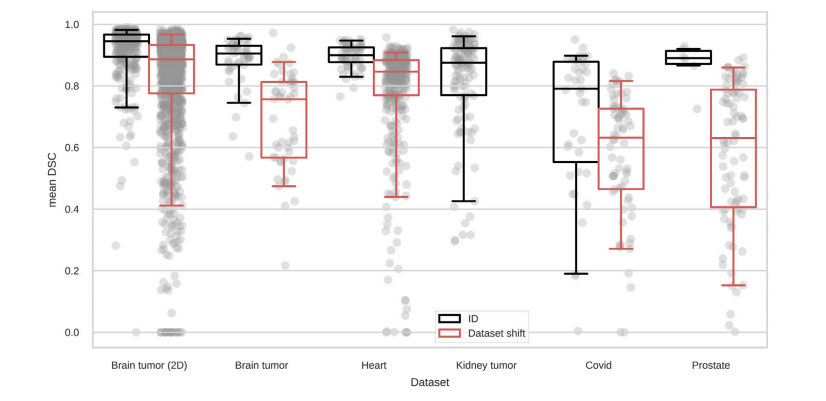

Fig. 2. Segmentation performance of a single U-Net on the test sets. Boxes show the median and IQR, while whiskers extend to the 5th and 95th percentiles, respectively. Eachdataset contains samples drawn from the same distribution as the training set (in-distribution, ID) and samples drawn from a different data distribution (dataset shift) with thesame structures to be segmented. Usually, the performance on the in-distribution samples is higher than on the samples with distribution shift, but especially for the Kidney tumor(which lacks dataset shifts) and Covid datasets, there are also several in-distribution failure cases.

图2. 单一U-Net模型在测试集上的分割性能。箱线图显示中位数和四分位间距(IQR),而胡须分别延伸到第5和第95百分位数。每个数据集包含来自与训练集相同分布的样本(分布内,ID)和来自不同数据分布(数据集偏移)的样本,且具有相同的分割结构。通常,分布内样本的性能高于具有分布偏移的样本,但特别对于肾脏肿瘤(没有数据集偏移)和Covid数据集,仍然存在一些分布内的失败案例。